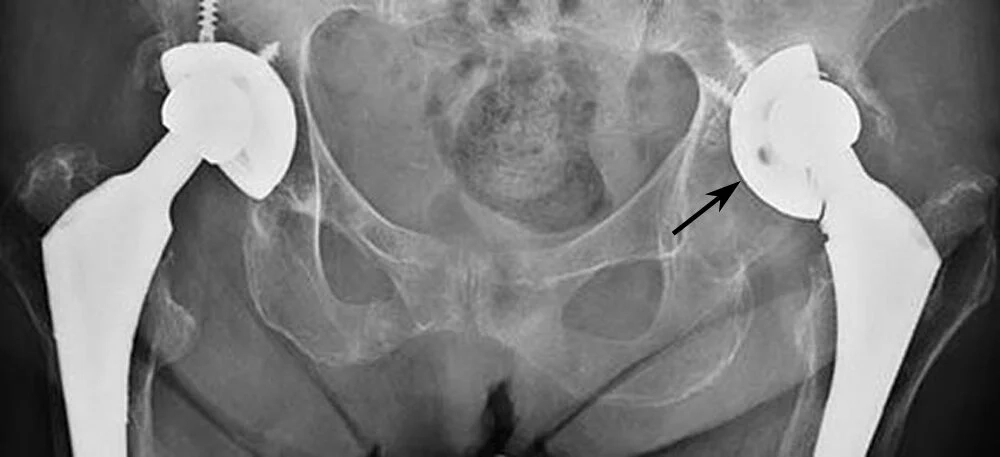

→ Acetabular cup – a metal shell fixed into the hip socket

→ Liner – typically polyethylene (plastic), ceramic, or metal

→ Femoral stem – a metal implant placed inside the thigh bone

→ Femoral head – a ball (ceramic or metal) that fits onto the stem

Fixation may be cemented or uncemented, depending on bone quality, patient factors, and surgeon preference.

A typical hip replacement consists of:

- Cup (acetabular component) – fits into the pelvis

- Liner – a smooth bearing surface

- Stem (femoral component) – fits into the thigh bone

- Ball (femoral head) – fits onto the stem

Implants can be:

- Cemented

- Uncemented

- Hybrid (one cemented, one uncemented)

- Your implant choice will be based on bone quality, anatomy, age and activity goals.